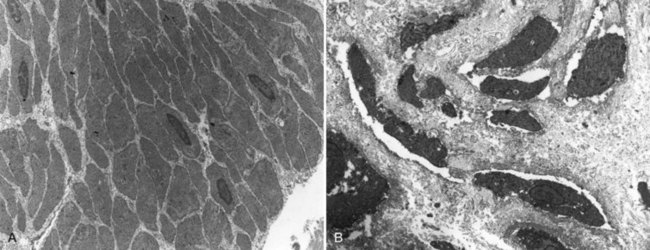

Several interesting aspects of the microstructure of the bladder in children with bladder exstrophy were noted by Mathews and colleagues (2004) using specimens obtained from children with bladder exstrophy at various stages of reconstruction (newborn bladder closure, bladder neck reconstruction, augmentation cystoplasty). At the cellular level, important differences were noted. Caveoli, which are important intracellular structures involved in cell-cell signaling, were found to be normal in the patients with a successful closure and improvement in bladder capacity and significantly lacking in the patients who required eventual augmentation cystoplasty (Fig. 124–11). In addition, the ultrastructure of cells in the patients in whom closure failed was noted to be abnormal.

Figure 124–11 Ultrastructural changes noted in the exstrophic bladder. A, Normal muscle and nerve profiles in the newborn bladder. B, Following failure of prior closure, significant deterioration is noted with increased intercellular collagen and degenerating muscle and few nerve profiles.

(From Matthews RI, Wills M, Perlman E, et al. Neural innervation of the newborn exstrophy bladder: an immunohistological study. J Urol 1999;162:506.)